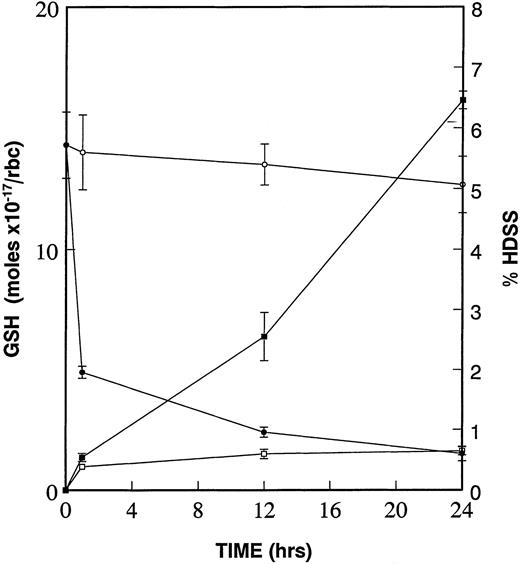

Due to the increased deposits of heme and free iron on the cytoplasmic surface of the high density SS erythrocyte membrane and the resultant formation of superoxide, peroxides, and hydroxyl radicals,6,23,24 we have proposed that the diminished levels of GSH in these same dense cells25,26 is critical to oxidative damage to β-actin and other target proteins.15We further proposed that this oxidative damage to β-actin, and other targets, leads to the formation of dense cells and ISCs. To test this hypothesis, we incubated low density sickle cells at 4°C in the presence and absence of 1.0 mmol/L CDNB. CDNB lowers GSH levels within erythrocytes by forming an irreversible adduct, 2,4-dinitrophenol-S-glutathione.27 As shown in the kinetic experiments presented in Fig 3, there is a rapid decrease in GSH levels even after 1 hour of incubation with CDNB, reaching a 90% decrease after 24 hours. The percentage of high density cells (those found in the 60% and 65% Percoll layers) increases constantly at 1 hour, 12 hours, and 24 hours CDNB treatment. Therefore, diminishing GSH levels in CDNB-treated cells is sufficient to cause cellular dehydration.

Diminishment of GSH leads to formation of dense cells. Percent of high density cells (% HDSS) formed were calculated and plotted after density separation via Percoll gradients of SS RBCs, which underwent incubation at 4°C of low density (45% Percoll layer) sickle cells without (−□−□−) or with (−▪−▪−) 1 mmol/L CDNB. Mol concentrations of GSH were determined in the same RBCs in the absence (−○−○−) and in the presence (−•−•−) of 1 mmol/L CDNB. Data is presented as mean ± standard error of four independent experiments. Values for GSH and HDSS were statistically significant (P < .05) at 1 hour, 12 hours, and 24 hours when comparing ± CDNB samples.

Diminishment of GSH leads to formation of dense cells. Percent of high density cells (% HDSS) formed were calculated and plotted after density separation via Percoll gradients of SS RBCs, which underwent incubation at 4°C of low density (45% Percoll layer) sickle cells without (−□−□−) or with (−▪−▪−) 1 mmol/L CDNB. Mol concentrations of GSH were determined in the same RBCs in the absence (−○−○−) and in the presence (−•−•−) of 1 mmol/L CDNB. Data is presented as mean ± standard error of four independent experiments. Values for GSH and HDSS were statistically significant (P < .05) at 1 hour, 12 hours, and 24 hours when comparing ± CDNB samples.